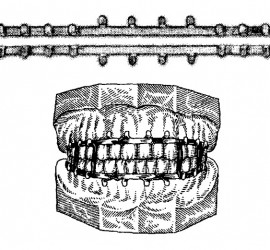

Цемент поликарбоксилатный (ТУ 64-2-275-78) выпускается Харьковским производственным объединением «Стома» (Украина). Предназначен для пломбирования молочных зубов и временных пломб, в качестве прокладок под постоянные пломбы из амальгамы, пластмассы и силикатного цемента, а также для фиксации вкладок, различных видов коронок, небольших мостовидных протезов и ортодонтических аппаратов. Поликарбоксилатный цемент выпускается в виде комплекта […]